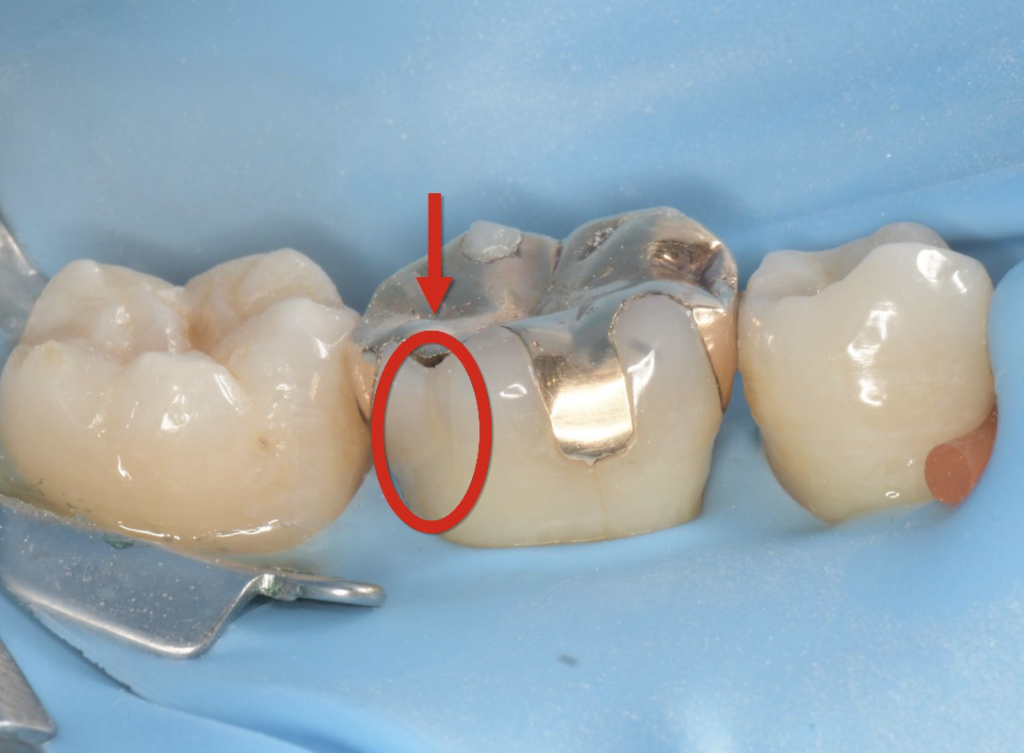

その後ラバーダム防湿を行い、インレーと呼ばれる金属を除去。

その際に歯に細かなヒビ(クラック)が確認されました。

歯のヒビは、日常的な食いしばりや歯ぎしり、硬いものを噛んだ際の負担などによって

生じることがあります。見た目では分かりにくく、

気づかないうちに進行してしまうことも少なくありません。

この患者様の場合も、ヒビから細菌が侵入し、内部で虫歯が進行していました。

その結果歯の神経まで感染が及び、神経の治療が必要な状態となっていました。